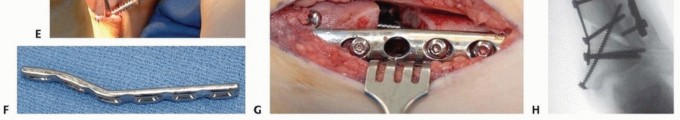

## The proposed plate is placed onto the distal tibia and positioned on the bone with the distal end of the plate just proximal to the physis. A site for the osteotomy is selected at the metaphyseal-diaphyseal junction as distal as possible while still allowing for adequate fixation of the distal fragment.

## The plate is then removed and an oscillating saw is used to create an osteotomy perpendicular to the long axis of the tibia (TECH FIG 5A).

##

TECH FIG 5 • A. Transverse osteotomy through distal tibia at metaphyseal-diaphyseal junction. B. Locking plate secured to the proximal fragment prior to derotation of the distal tibia. C. Image from distal of the thigh-foot angle showing correction of external tibial torsion prior to securing the distal fragment. D. Locking plate secured to distal tibia using combination of locking and nonlocking screws after correction of external tibial torsion.

## The plate is then placed once again along the tibia and secured to the tibial shaft (TECH FIG 5B). The distal tibia is then derotated to a position where the thigh-foot angle is neutral (TECH FIG 5C).

## The distal fragment is then secured to the plate using screws. If a locking plate has been selected to stabilize the osteotomy, locking screws should be used to secure the distal fragment to the plate (TECH FIG 5D).

## Adequate fixation should be used to allow weight bearing for transfers.

## Wound closure is carried out in a routine fashion, and immobilization can be achieved using either a short-leg cast or a walking boot.